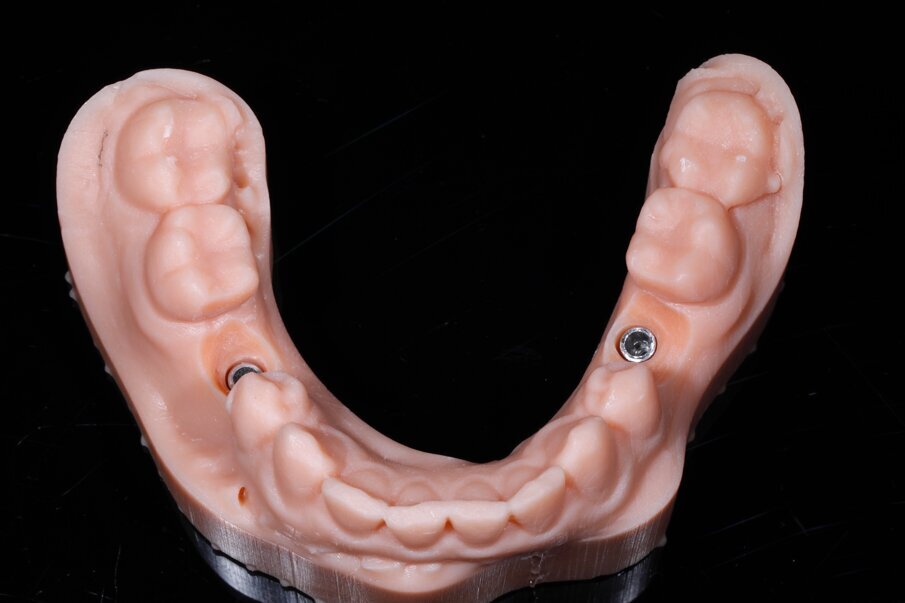

Fig. 12a_Il modello prototipato con stampante DWS XFAB realizzato in alta definizione con materiale Precisa 097 DWS technology.

Fig. 12b_La prova dei restauri nella fase di prefinitura.